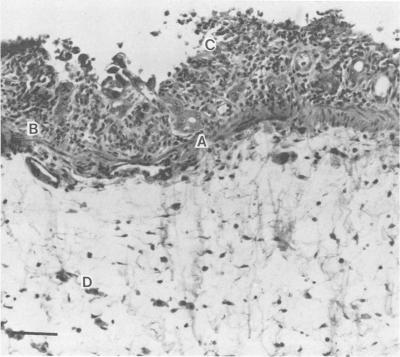

We tested the usefulness of the Removable Intestinal Tie Adult Rabbit Diarrhea model to establish Campylobacter jejuni infection in rabbits. The procedure involved ligation of the cecum, placement of a slip knot at the terminal ileum, and injection of the test inoculum into the mid-small bowel. The ends of the slip knot were externalized, and the tie was released 4 h later. Fifty-five rabbits received C. jejuni, and 16 received uninoculated medium as controls. Daily rectal swabs were positive for 2 weeks in infected rabbits. The diarrheal attack rate was 64% in infected rabbits and 0% in controls. Diarrhea was characterized by loose, mucus-containing stools after an incubation period ranging from 24 h to 6 days. When blood was obtained daily for culture from 30 rabbits for 4 days post-challenge, bacteremia was present in 96.3% 24 h after challenge but diminished to 5 of 19 (26.3%) at 96 h. Death occurred in 53% of rabbits and was always preceded by diarrhea. No control animal died. Only 5 of 35 animals experiencing diarrhea recovered. An indirect whole-cell enzyme-linked immunosorbent assay was used to determine serum immunoglobulin G responses. Mean titers rose from 1:198 preoperatively to 1:9,087 on day 28. Necropsy on eight infected and two control animals showed inflammatory lesions with ulceration in 62.5% and goblet cell hyperplasia in 75% of infected rabbits. We conclude that the Removable Intestinal Tie Adult Rabbit Diarrhea procedure is a simple, effective method to establish C. jejuni infection which mimics human disease.

我们测试了可移除肠道结扎成年兔腹泻模型在兔中建立空肠弯曲菌感染的实用性。该操作包括结扎盲肠、在回肠末端放置一个活结,并将测试接种物注入小肠中部。将活结的两端引出体外,4小时后松开结扎。55只兔接种空肠弯曲菌,16只接种未接种的培养基作为对照。感染兔的每日直肠拭子在2周内呈阳性。感染兔的腹泻发作率为64%,对照组为0%。腹泻的特征是在24小时至6天的潜伏期后出现稀便、含黏液的粪便。在攻毒后4天,每天从30只兔采集血液进行培养,攻毒后24小时菌血症发生率为96.3%,但在96小时时降至19只中的5只(26.3%)。53%的兔死亡,且死亡前均有腹泻。无对照动物死亡。35只出现腹泻的动物中只有5只恢复。使用间接全细胞酶联免疫吸附试验来测定血清免疫球蛋白G反应。平均滴度从术前的1:198升至第28天的1:9087。对8只感染动物和2只对照动物进行尸检,发现62.5%的感染兔有炎症性病变伴溃疡,75%有杯状细胞增生。我们得出结论,可移除肠道结扎成年兔腹泻操作是一种简单、有效的建立空肠弯曲菌感染的方法,该方法可模拟人类疾病。